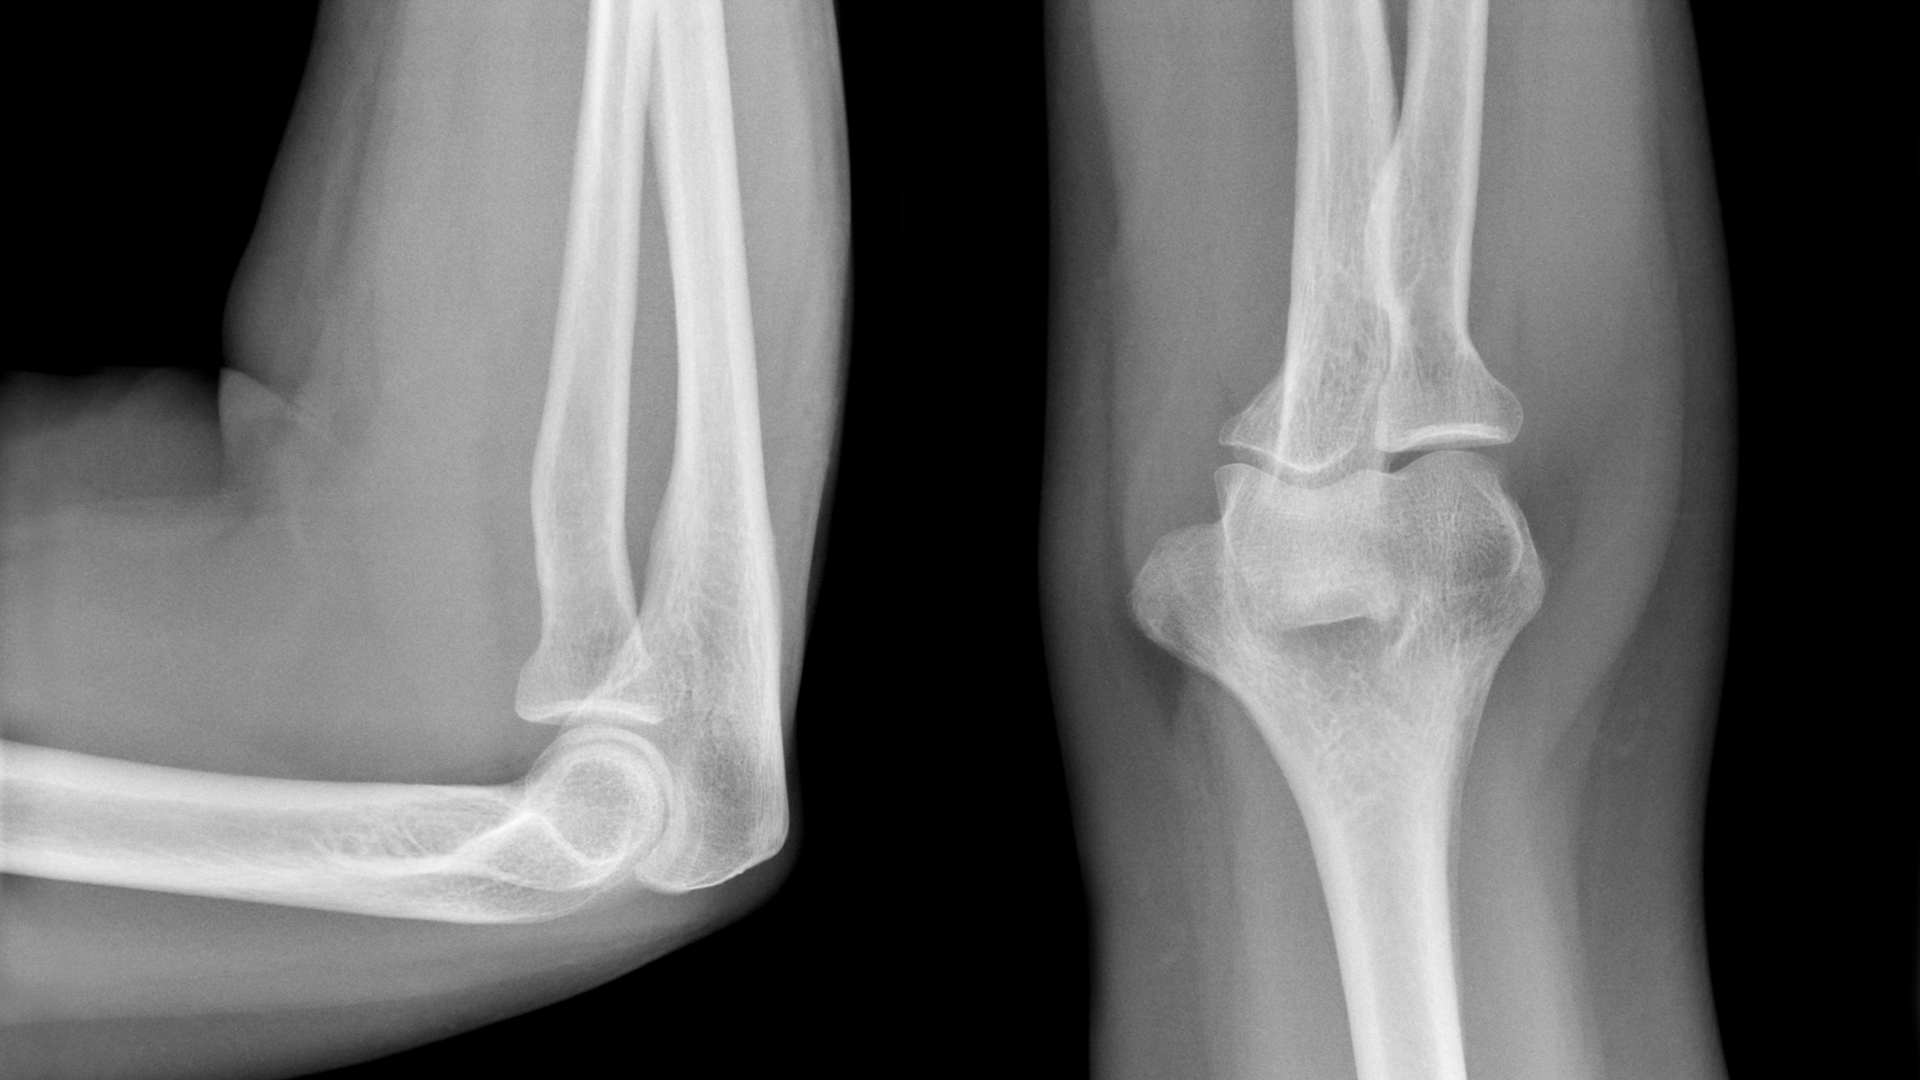

Các tổn thương do chấn thương

Đây là nhóm nguyên nhân phổ biến nhất:

- Gãy đầu xương quay.

- Gãy mỏm khuỷu.

- Trật khớp khuỷu.

Những tổn thương này thường xảy ra sau tai nạn hoặc té ngã và cần được phát hiện sớm để xử lý phù hợp.

Hình ảnh bình thường

Một phim X-quang khớp khuỷu bình thường thường có:

- Cấu trúc xương rõ nét.

- Khe khớp đều.

- Không có dấu hiệu lệch trục.

Dấu hiệu bất thường

Một số dấu hiệu có thể gợi ý vấn đề:

- Xuất hiện đường gãy.

- Lệch vị trí khớp.

- Hẹp khe khớp.

- Hình thành gai xương.